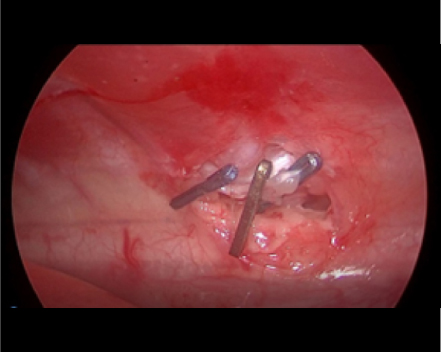

反対側も同じように剥離していきます。

必ず、反対側の胸管も確認できるところまで剥離します。(黒矢印)

反対側もクリップ3-4本止めて、結紮します。

これで胸管結紮は終了です